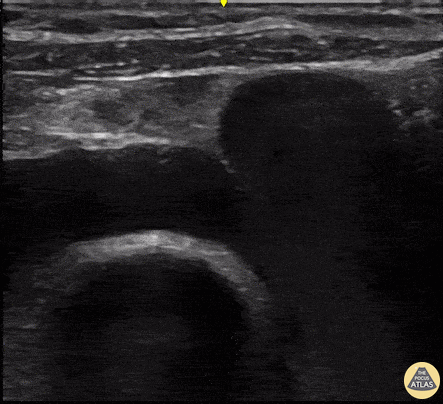

This POCUS revealss a supraclavicular long axis view of the subclavian vein. It is an ideal view for US-guided central venous access. Renato Tambelli, mergency Physician Hospital das Clínicas de Marília, Brazil. @R_Tambelli // @JediPocus